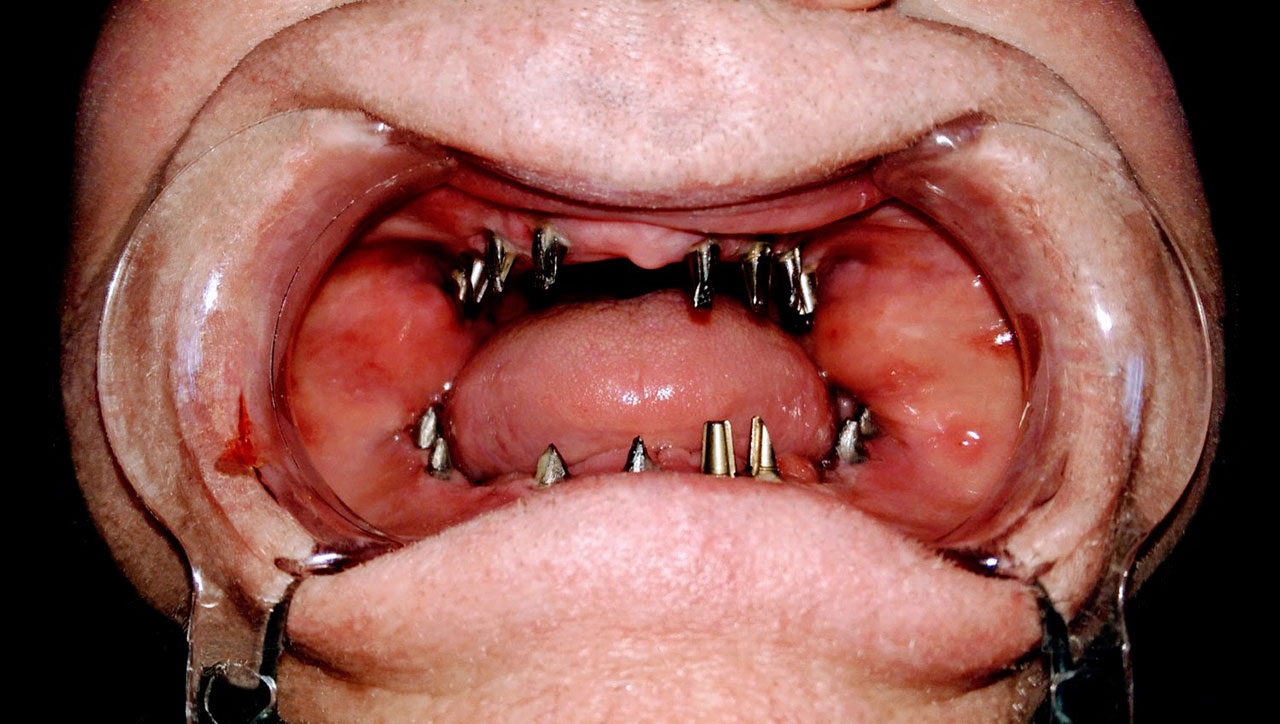

• esettanulmany-04

Impantáció előtt, súlyos fogágy pusztulás, gyulladás látható.